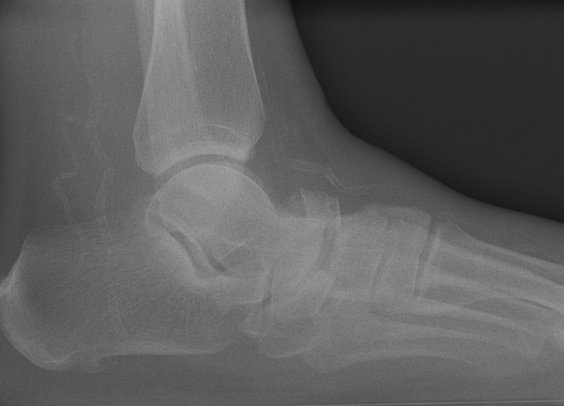

Return to Navicular (Tarsal) Fracture